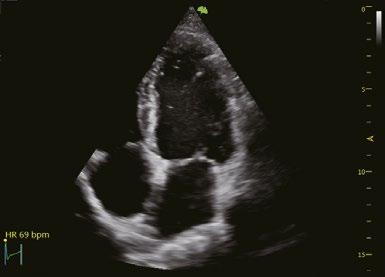

Apikale 4-Kammer-Ansicht zeigt segmentale und globale longitudinale Dehnung des linken Ventrikels

Mit einem Klick die Auswurfrate (EF) automatisch berechnen.